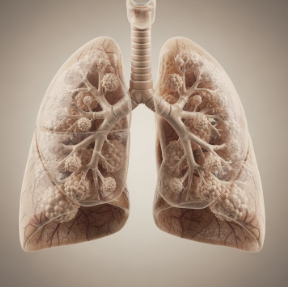

3단계: 만성 기관지염·COPD·기관지확장증

흡연과 대기 오염에 오래 노출된 경우, 3개월 이상 기침과 가래가 계속되는 만성 기관지염과 COPD가 중요한 가래가 생기는 원인이 된다. 기관지확장증처럼 하부기도가 반복 감염과 염증으로 늘어난 질환도 하루 종일 많은 양의 가래와 기침, 호흡곤란을 유발하는 심각한 가래가 생기는 원인이다.

특히 흡연자는 가래가 생기는 원인이 단순 감기가 아닌 만성 폐질환일 가능성이 높아 금연과 전문의 진료가 필수다.